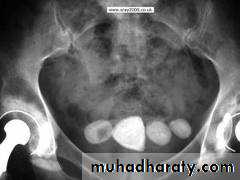

Dr. Sameer Abdul Lateef* Infestation by Schist. Haematobium.

*The ova deposited into sub-mucosa of urinary bladder and to less extent at the wall of ureters .*The ova calcify and excrete toxin producing necrosis of tissue lead to granulomatous tubercles and extensive fibrosis .

*Calcification is very common and important diagnostic findings. Very common in bladder ,less frequent in lower ureters ,but in advanced case involve the whole length of ureter .

*The appearance depends on degree of fullness of bladder ; thin linear opacity outlining bladder wall.

Empty bladder shows crowded linear opacities with calcified plaques.

Urinary Schistomiasis